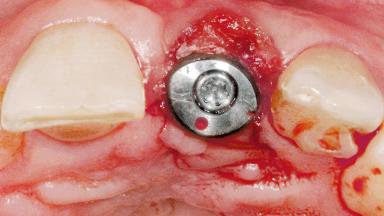

Late Flapless Placement of an Implant in a Maxillary Left Central Incisor Site

A 39-year-old male patient presented with a chief complaint of discomfort and gingival discoloration around his maxillary left central incisor. He was in good general health and was a non-smoker. His past dental history was significant because of the traumatic fracture of tooth 21 in a sporting accident at age 13. Initial dental treatment included endodontic therapy and a full-coverage restoration. The patient became symptomatic 5 years later, when structural failure of the tooth resulted in the dislodgment of the crown. Endodontic retreatment, apical surgery, and post-and-core restoration were performed.

| # of Implants | 1 |

| Type of Implants | One-Piece |

| Attachment | One-Piece |

| Bone Volume | Deficient horizontally, requiring prior grafting |